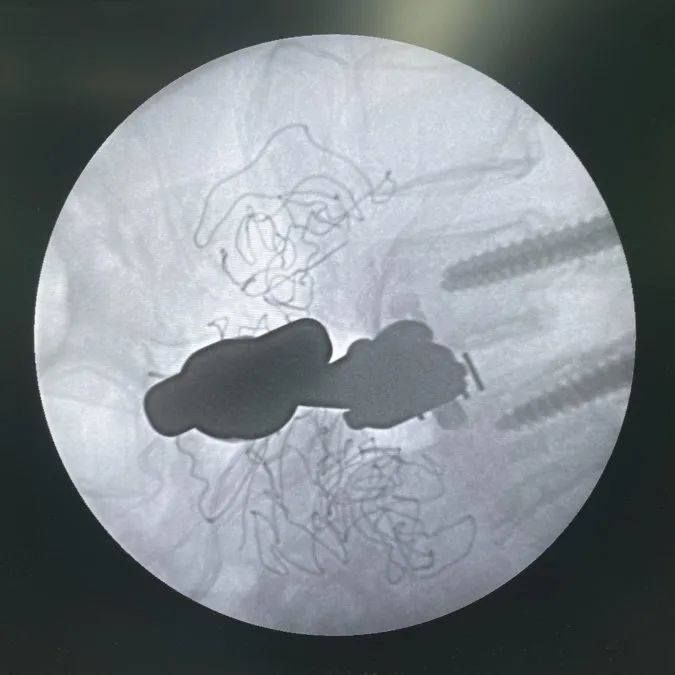

最終透視

L4/L5植入Uni-L自穩(wěn)定型腰椎融合器

L3/L4常規(guī)OLIF融合器植入

L3/L4 、L4/L5椎間植骨